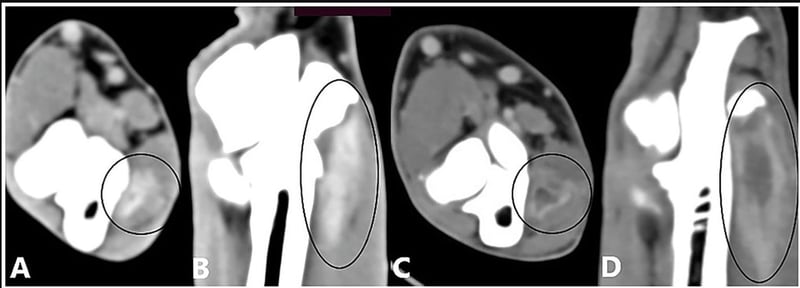

Oncology

+1

Apr 26, 2026

•

2 min read